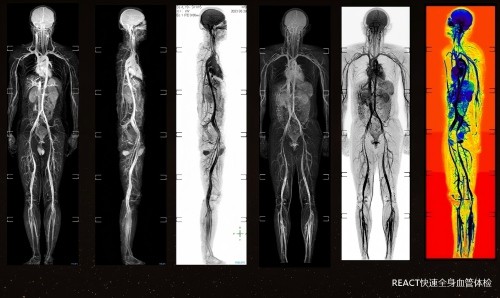

(1)无创大血管筛查:全程无电离辐射、无需造影剂,真正实现零过敏风险、零创伤的安全检查。